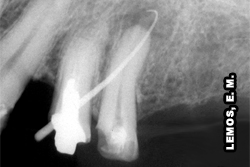

Por vezes, durante a inspeção clínica com o uso do espelho e explorador é possível constatar fraturas coronárias e/ou radiculares, porém em alguns casos, necessário se faz, lançar mão de recursos alternativos, como o teste de mordida com instrumentos oclusais para melhor investigar a possibilidade de fraturas (completas ou incompletas) sem alterações clínicas visíveis em dentes com sensibilidade à mastigação. A radiografia periapical nesses casos não permite visualizar ou interpretar tais fraturas, salvo se os fragmentos estiverem separados. Dente 25 apresentando fratura proximal oblíqua oclusal-palatina e, dente 26 fratura da restauração em amálgama. Uma cunha de madeira foi colocada no dente 25 para afastar os fragmentos durante a tomada fotográfica, figura ao lado.

![]() |